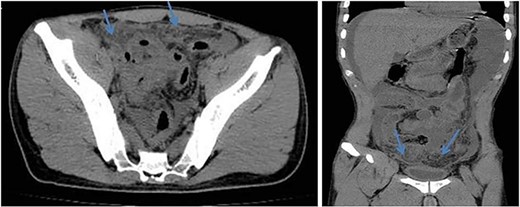

A computed tomography scan without contrast (due to elevated s.creatinine of 2.18) revealed a moderate to severe amount of free fluid in the abdominal and pelvic cavities. The appendix was perforated. The juojenal bowel loops and the rectum showed circumferential wall thickening mostly due to inflammatory process (Figs 1 and 2).

Axial (left) and coronal (right) views of abdomen CT scan without contrast show dirty fat planes closely related to the urinary bladder walls (mass formation).